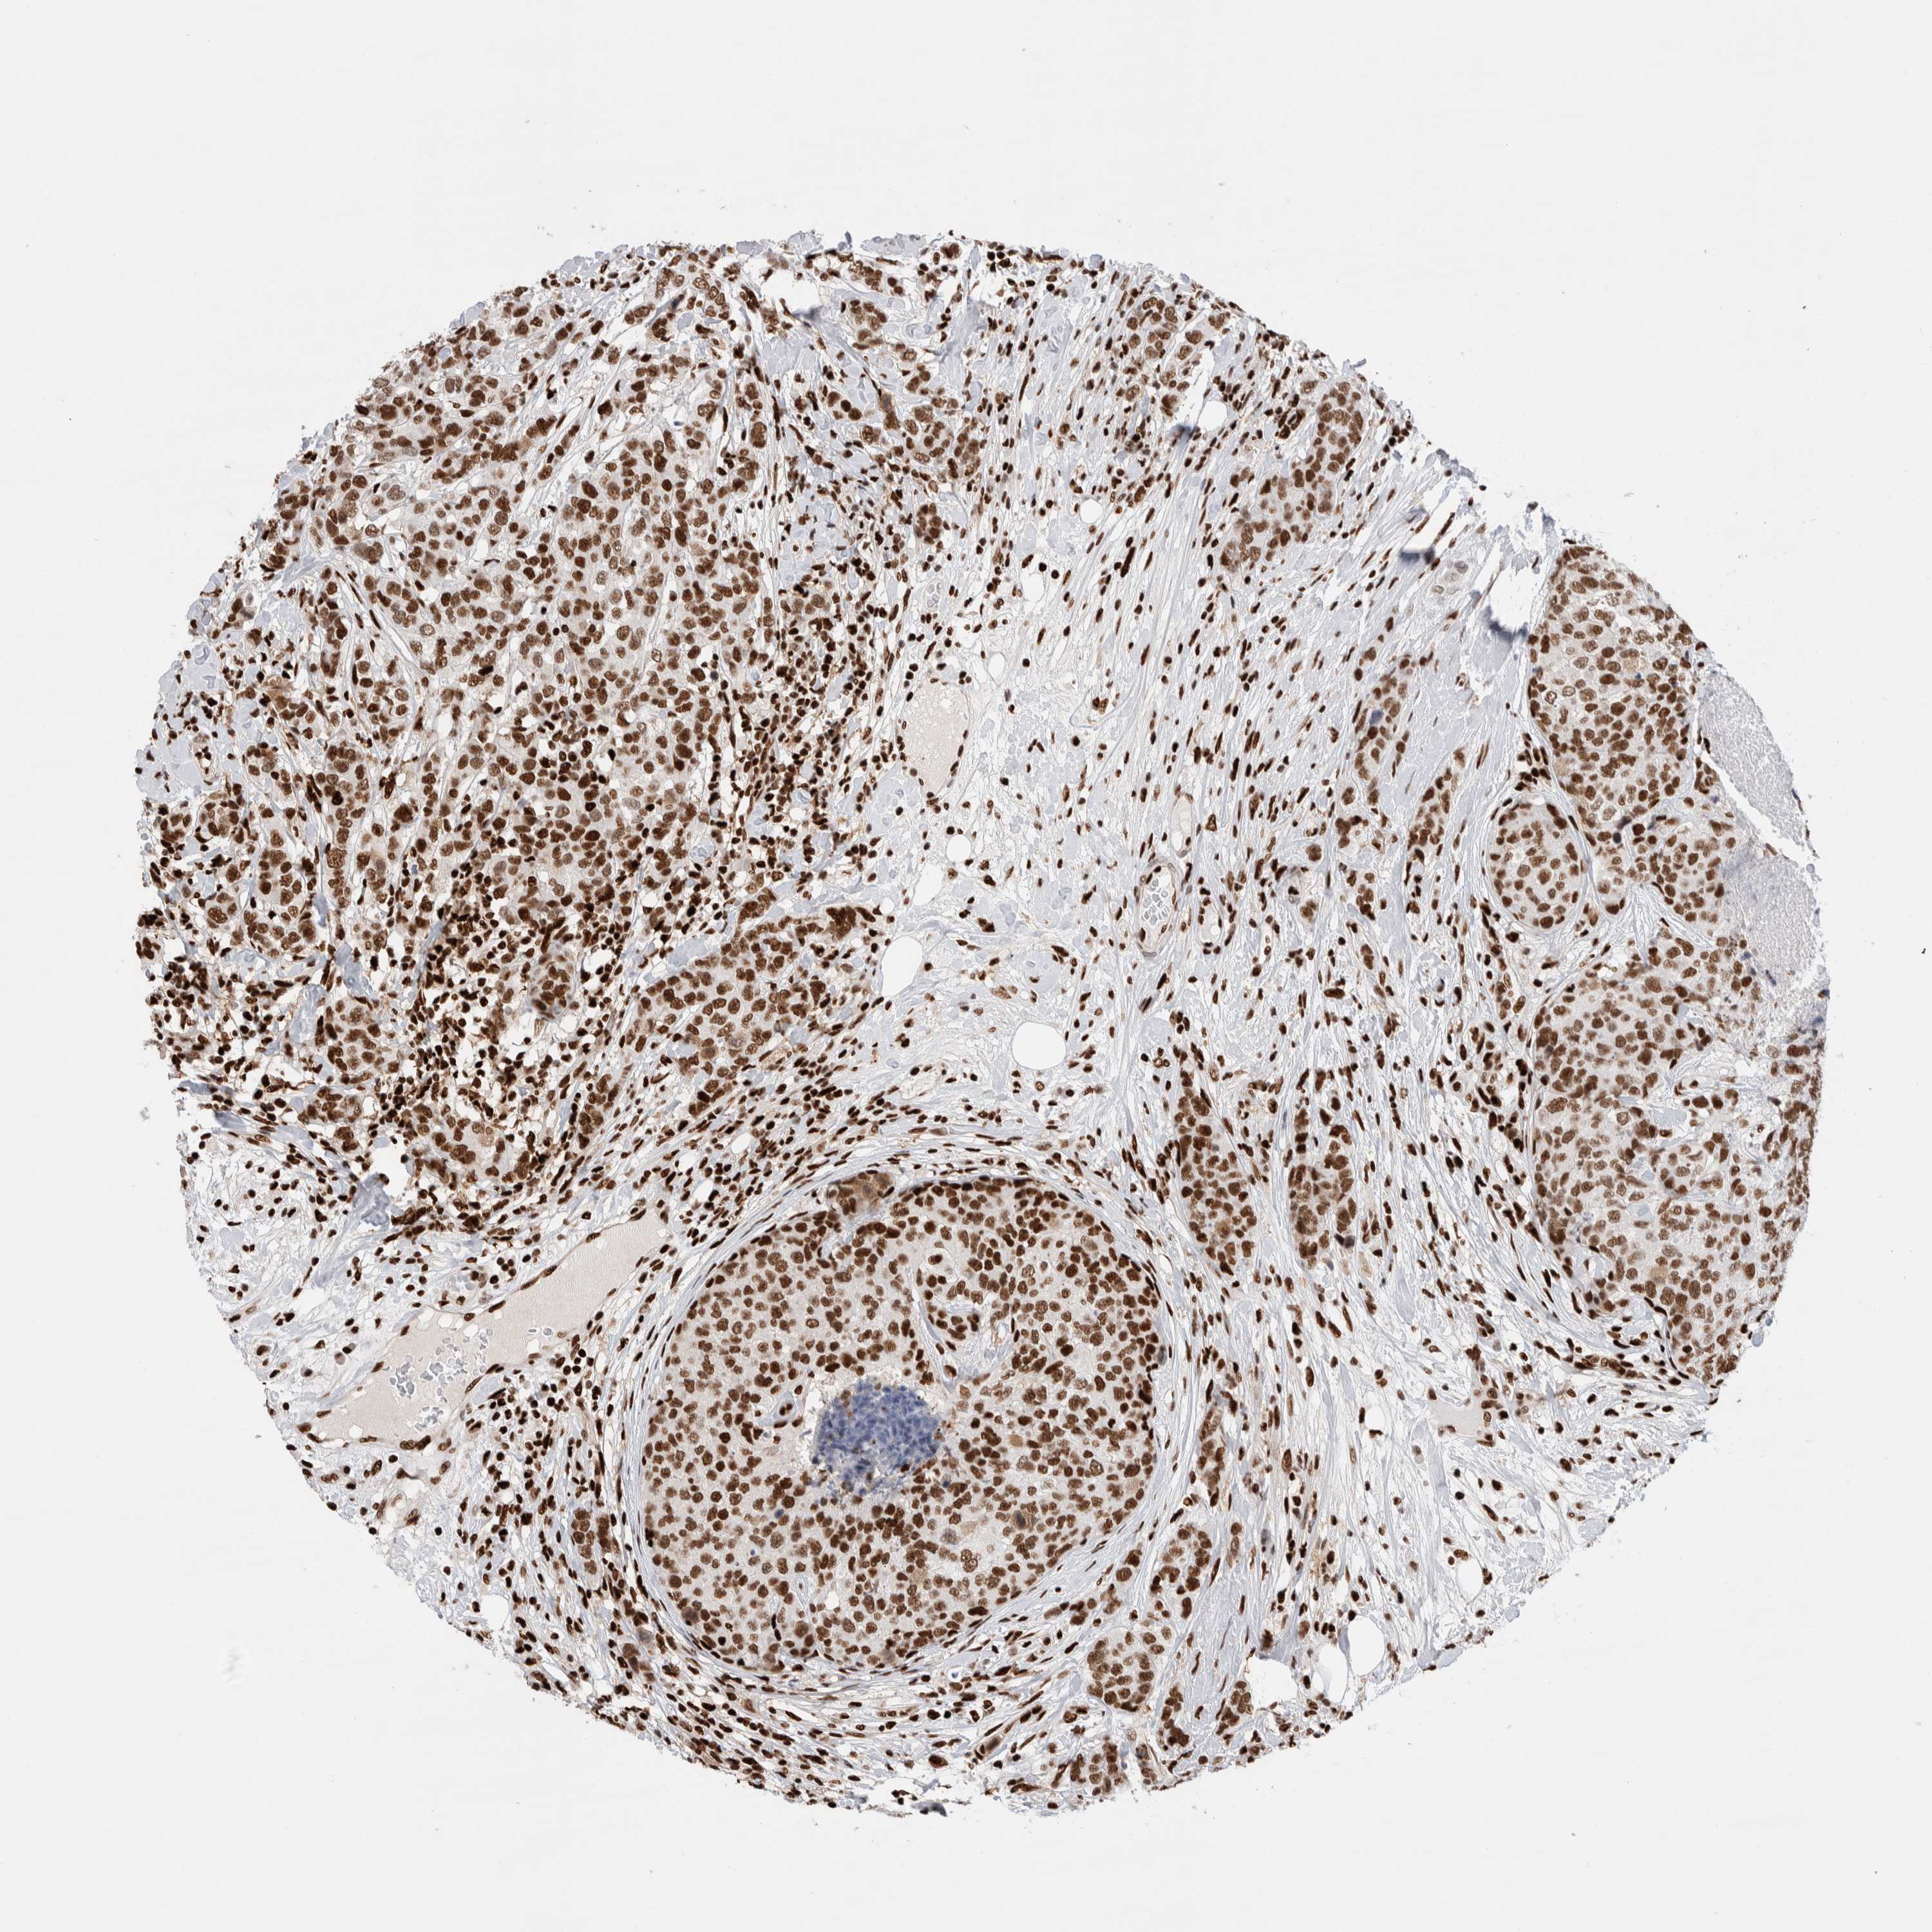

BRCA TCGA BRCA VALIDATION PROTEIN EXPRESSION